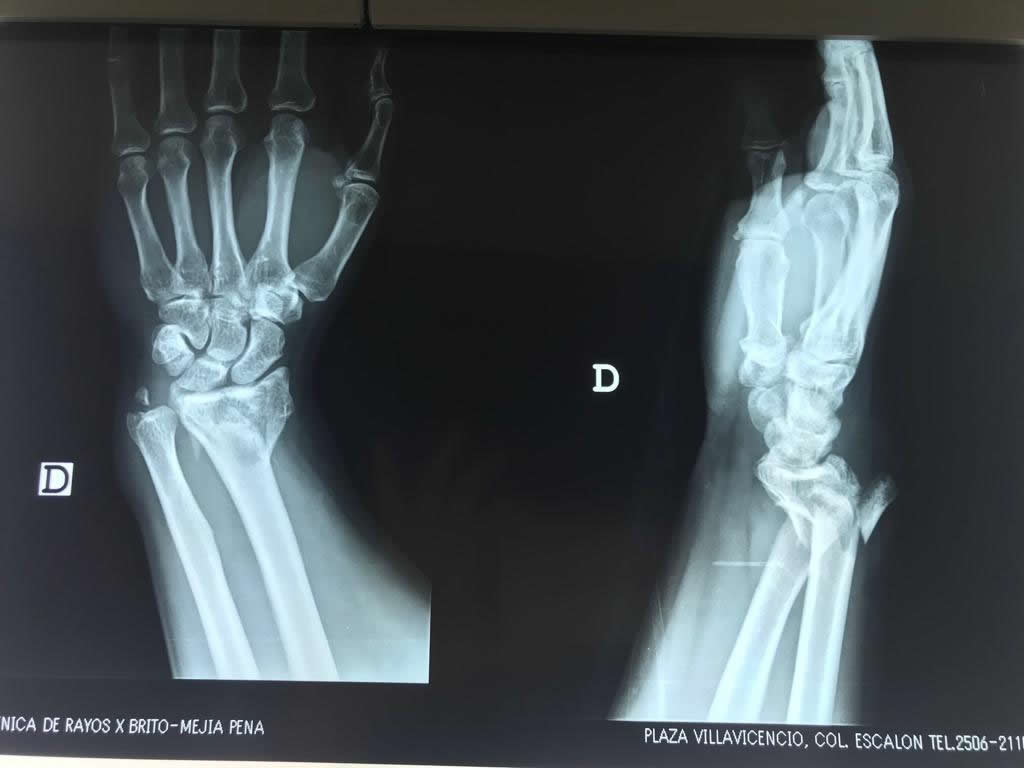

Cirugías de Codo - Cirugías de Muñecas y Manos

Los procedimientos más comunes en cirugía de la mano son aquellos destinados a reparar traumatismos, incluyendo lesiones de tendones, nervios, vasos sanguíneos, y articulaciones; huesos fracturados; y quemaduras, cortes, y otros daños de la piel.